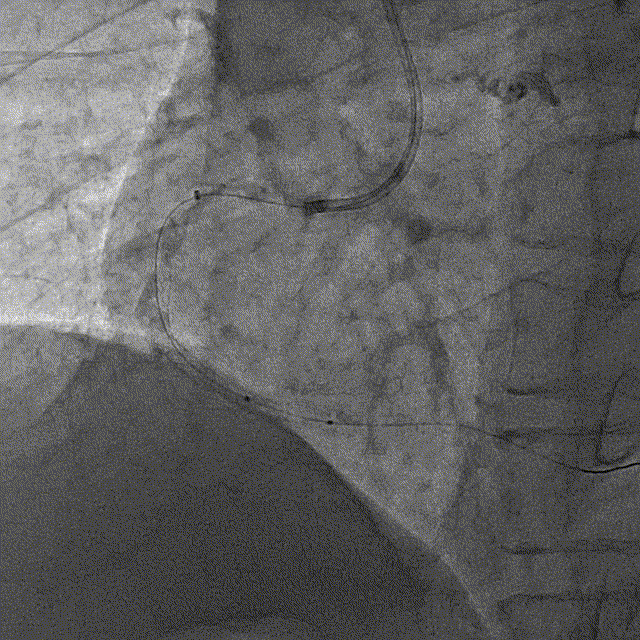

冠脉造影

冠脉造影结果:LM外膜钙化,内膜不光滑,中段狭窄90%,TIMI3级。LCX外膜钙化,内膜不光滑,TIMI3级。RCA外膜钙化,内膜不光滑,近段狭窄80%,中段狭窄90%,可见破损斑块,TIMI3级。